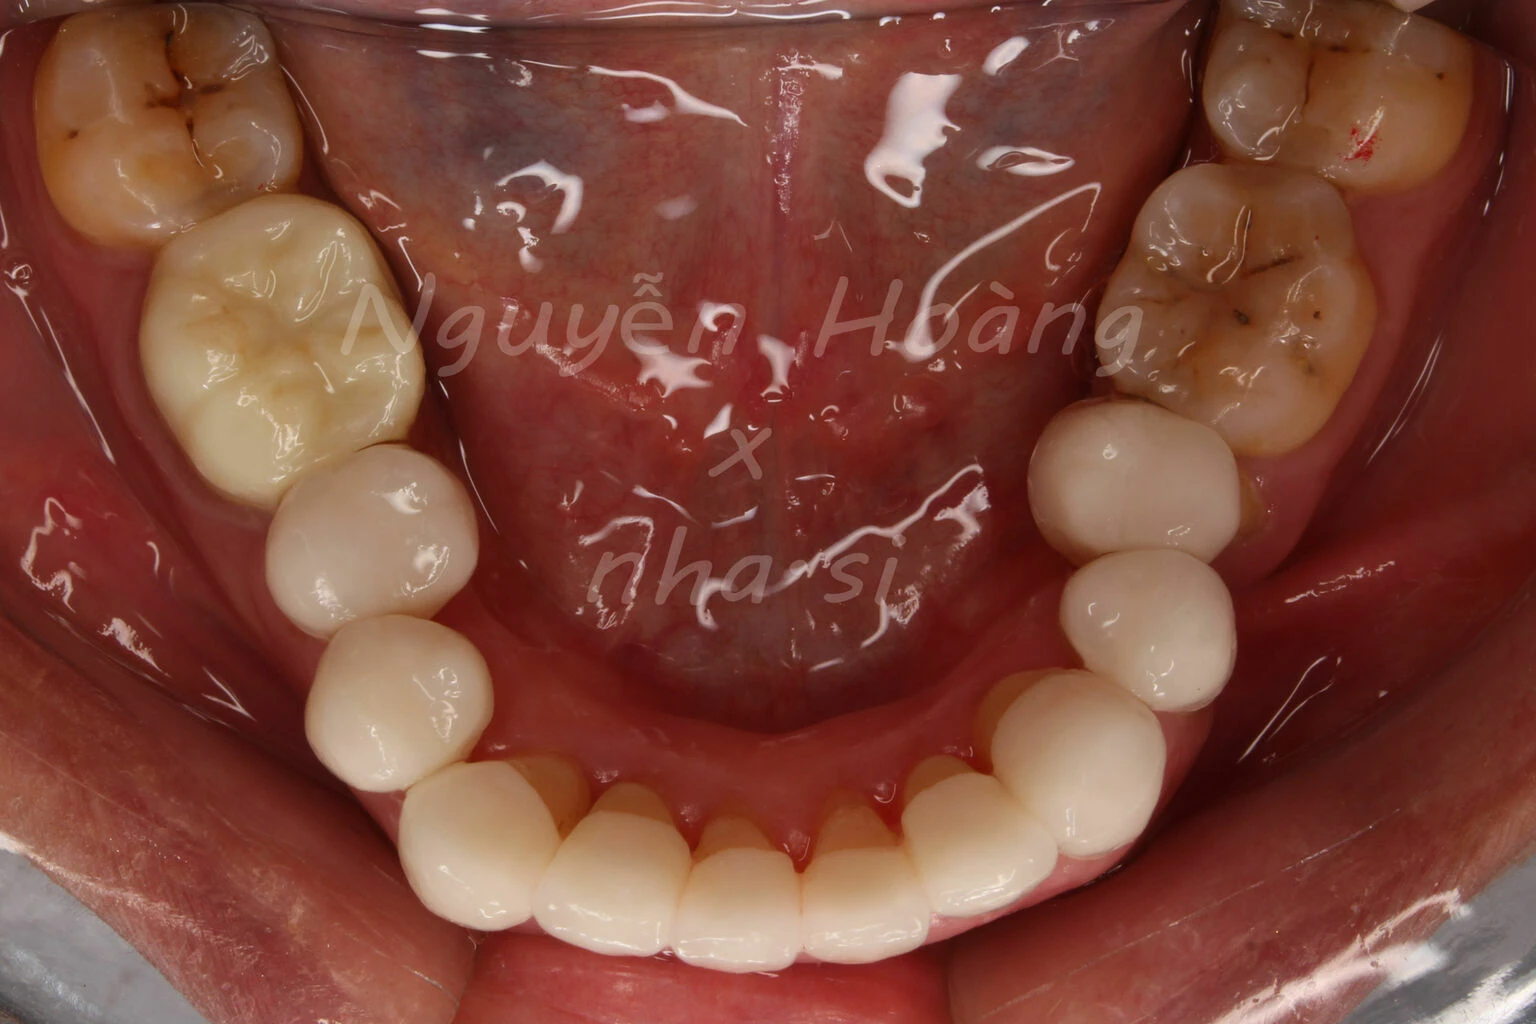

Hình 5: Sau gắn. Khách hàng hài lòng với bộ răng sứ thẩm mỹ.Nhìn từ phía ngoài, vị trí răng 5 được chụp sứ “làm đầy” hơn so với vị trí răng cũ.